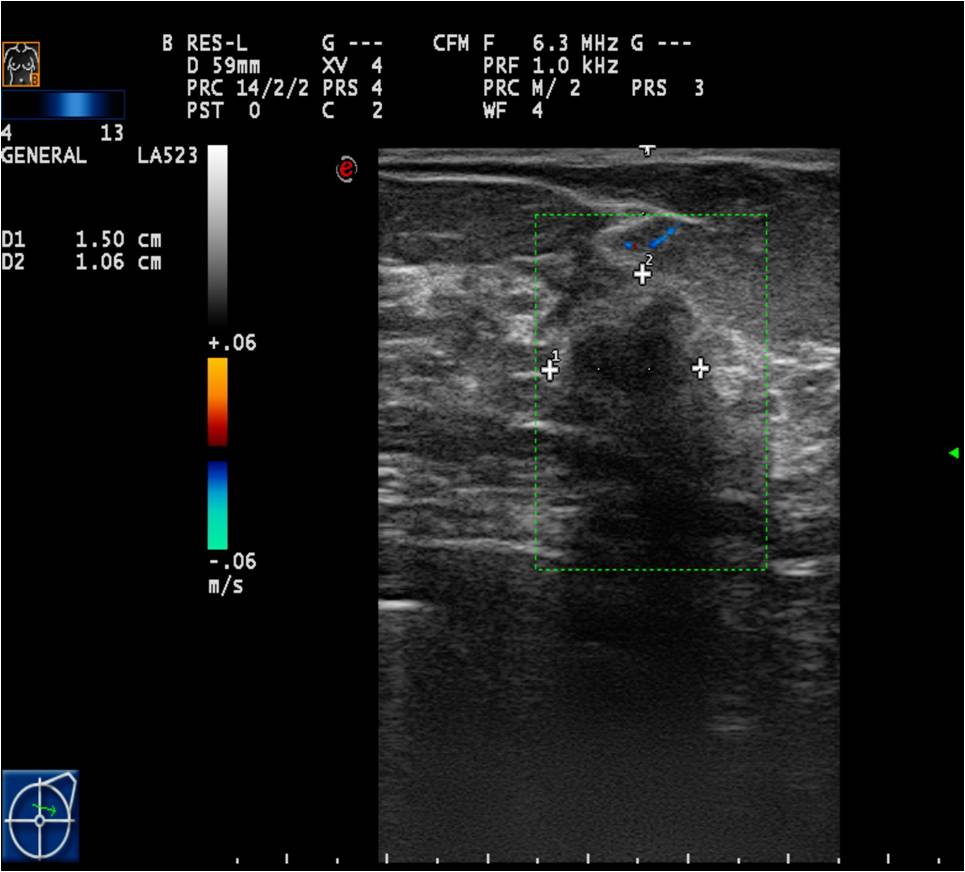

Ultrasonography can help in their differentiation; can depict anechoic cystic lesions (Picture17.) or solid masses (Picture 18.). These lesions usually each have a smooth, sharp edge and echo-enhancement can appear behind them. Rarely, cysts contain tumors. (Picture19.).

Ill-defined margins, with uneven contours and blurred edges are usually characteristic of malignant lesions. During ultrasound examination echo-attenuation occurs frequently behind these inhomogeneous hypo-echogenic masses (Picture 20).

Doppler examinations: can only be used as auxiliary exams. It depicts higher vascularization in malignant tissues.